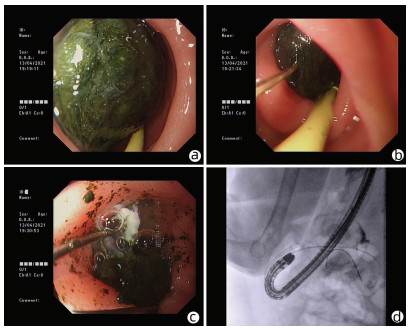

Successful treatment of Bouveret ' s syndrome due to giant duodenal gallbladder stones through the anterior wall of the stomach: A case report

Xu CHEN, Lunxu LI, Bing QI, Qingkai ZHANG, Guixin ZHANG, Shuang LI, Dong SHANG

2022, 38(3): 636-638. DOI: 10.3969/j.issn.1001-5256.2022.03.028

Abstract(974) HTML (241) PDF (2628KB)(64)

Abstract: